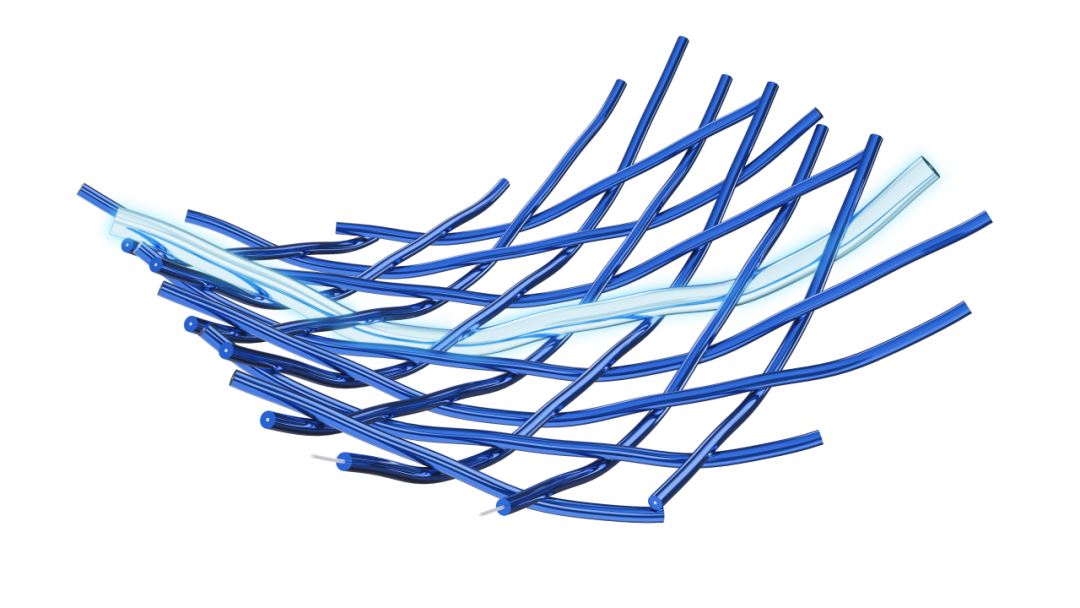

Tubridge Plus血流导向密网支架是微创脑科学的经典血流导向密网支架Tubridge的第二代,进行了诸多升级:两维3D、全程显影;全系列适配27微导管;推送阻力明显下降等等。

两维3D,全新升级

Tubridge Plus显影性能飞跃